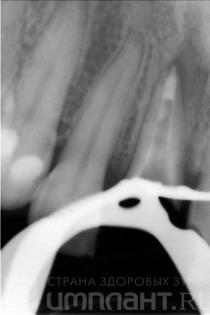

Cu toate acestea, atunci când studiază razele X, devine clar că rădăcina este suficient de lungă, că nu există nici o inflamație în partea superioară.

După 2 săptămâni, sa efectuat un tratament endodontic repetat, a fost instalat un știft din fibră de sticlă.